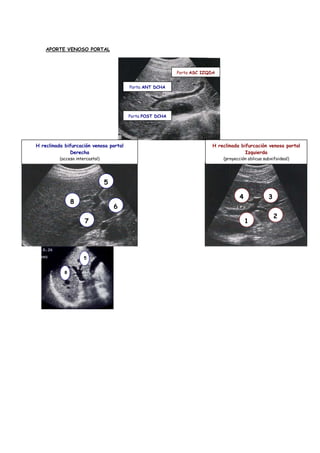

APORTE VENOSO PORTAL

Porta ASC IZQDA

Porta ANT DCHA

Porta POST DCHA

H reclinada bifurcación venosa portal                                    H reclinada bifurcación venosa portal

Derecha                                                                  Izquierda

(acceso intercostal)                                               (proyección oblicua subxifoideal)

5

4             3

8

6

2

7                                                                  1

APORTE VENOSO PORTAL Porta ASC IZQDA Porta ANT DCHA Porta POST DCHA H reclinada bifurcación venosa portal H reclinada bifurcación venosa portal Derecha Izquierda (acceso intercostal) (proyección oblicua subxifoideal) 5 4 3 8 6 2 7 1 5 8